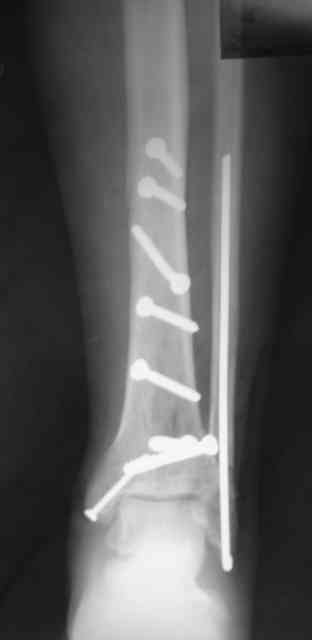

Re: Сложный внутрисуставной перелом голени

Антон Лебединец 29 Апрель 2007, 22:01

Рентгенограммы